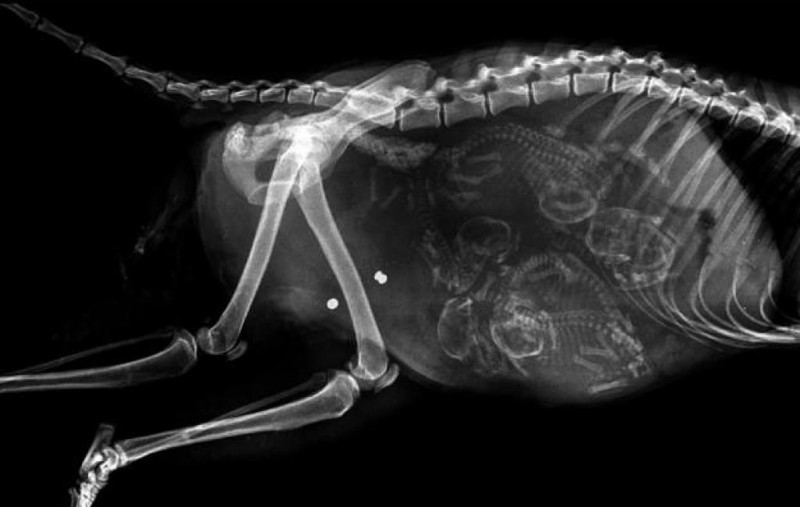

Մենք բոլորս լավ պատկերացնում ենք, թե ինչպես է անցնում մարդու հղիությունը, և շնորհիվ ժամանակակից տեխնոլոգիաների՝ կարող ենք տեսնել երեխային մայրիկի արգանդում հղիության ամենավաղ փուլում։ Իսկ ինչպե՞ս է ընթանում կենդանիների հղիությունը։ Մասնագետները, ովքեր հոգ են տանում հղի կենդանիների մասին, ներկայացրել են նրանց ռենտգենային և ուլտրաձայնային լուսանկարները, որոնք ձեր դատին է հանձնում «twizz.ru» կայքը։

Կատու